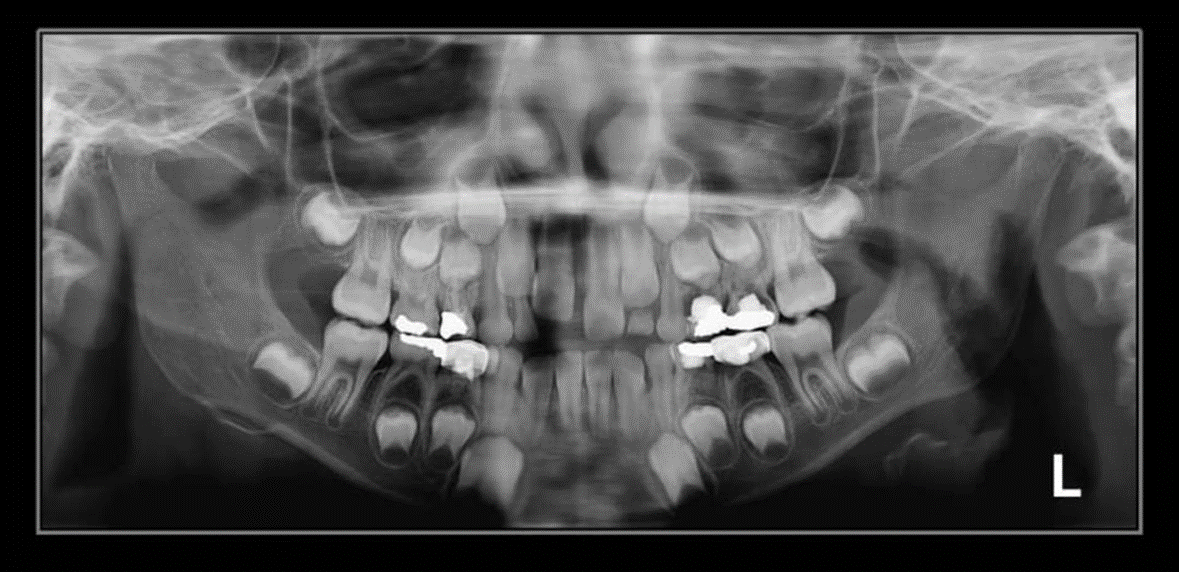

4. How old is the patient with the following X ray?